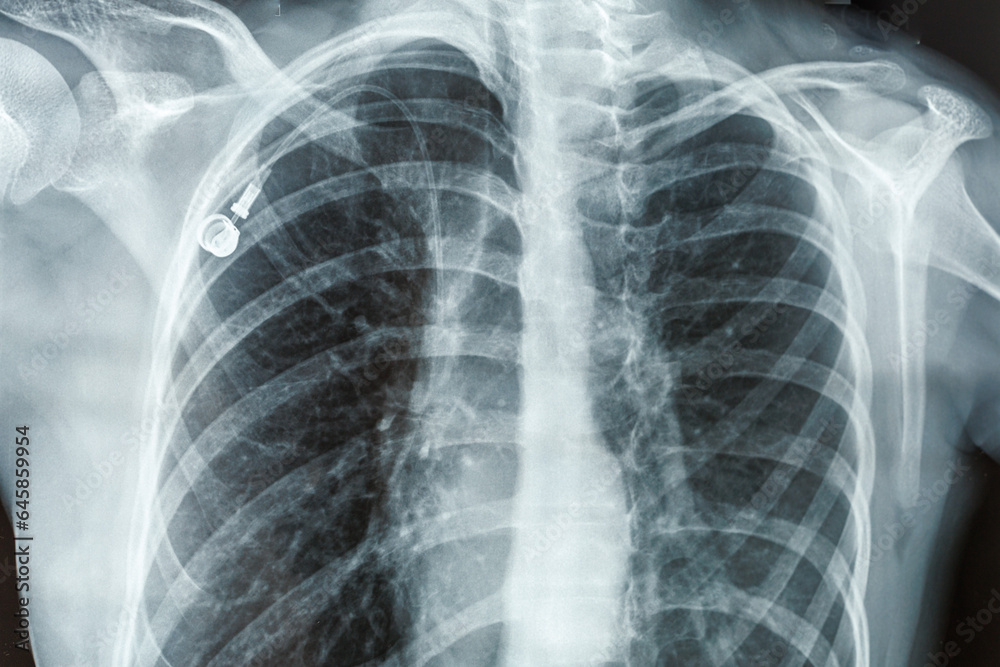

From stock.adobe.com

Xray of a person s lungs and breast with Port Catheter. Virus, cancer Can A Chest Port Move Out Of Place Is the port unsightly, or can you barely see it? A port can be left in place for weeks, months, or even years, but it is typically removed after chemotherapy treatment. Your port can stay in place for years. They also will remove it if it gets infected. Once the chemo port is in place and chemotherapy has begun, the. Can A Chest Port Move Out Of Place.